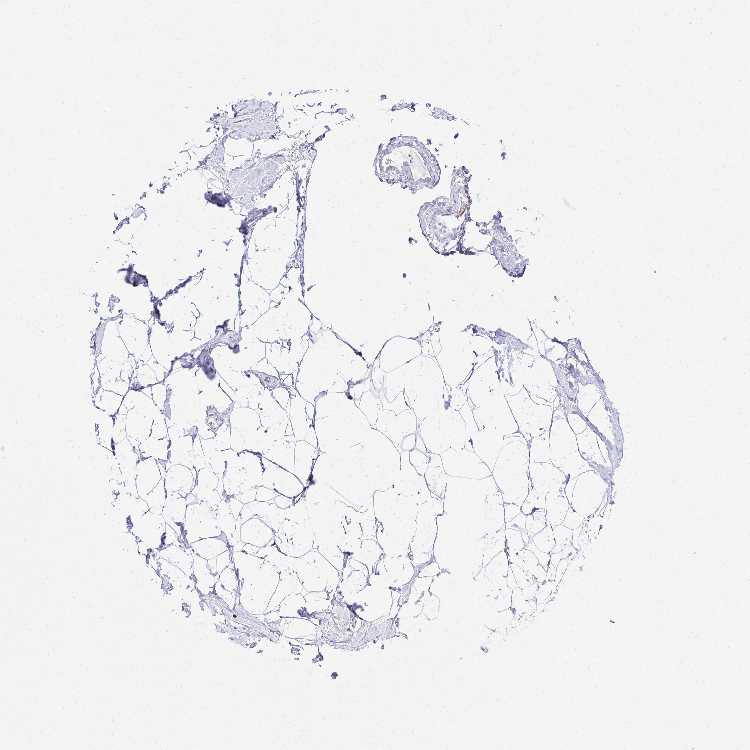

BREAST - Antibody stainingi

Antibody staining in the annotated cell types in the current human tissue is reported as not detected, low, medium, or high, based on conventional immunohistochemistry profiling in selected tissues. This score is based on the combination of the staining intensity and fraction of stained cells.

Each image is clickable and will lead to virtual microscopy that enables deeper exploration of all samples and also displays staining intensity scores, fraction scores and subcellular localization as well as patient and tissue information for each sample.

Antibody HPA062743

Adipocytes Not detected

Glandular cells Not detected

Myoepithelial cells Not detected